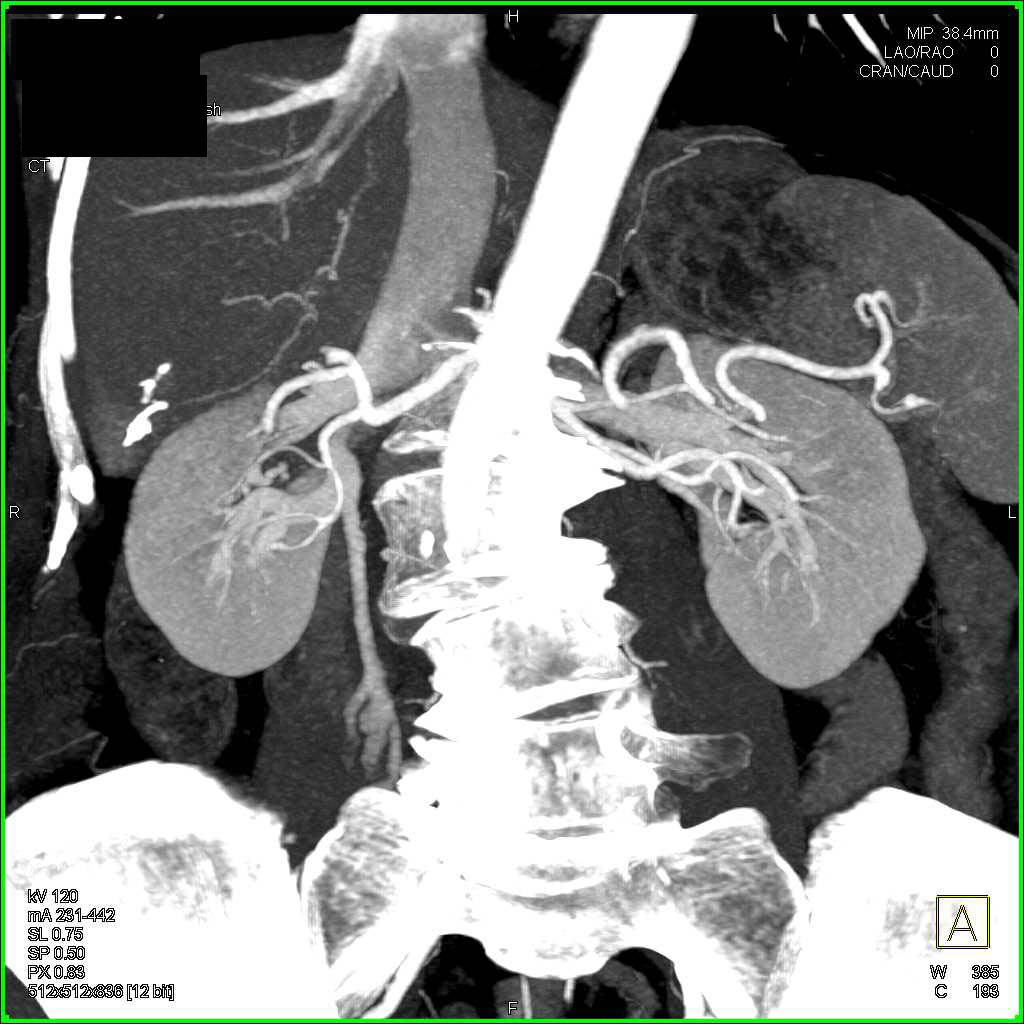

Active Bleed in the Gastric Antrum